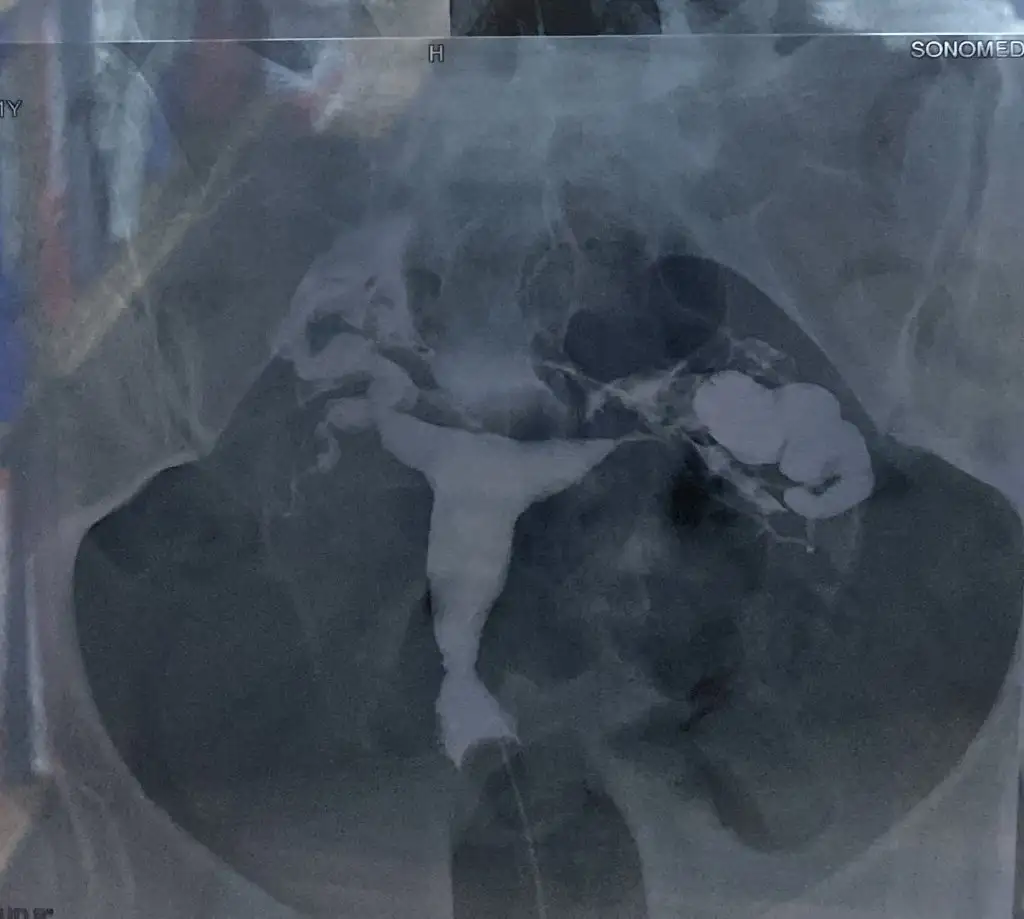

Ayy dur deniyeceğm oldu mu bilmiyorum şöyle cekmiştim öncedenMerhaba görüntünü varsa yükleyebilir misiniz mümkünse görüntüyü merak ettim![]()

Sanırım olmadı ben göremedimAyy dur deniyeceğm oldu mu bilmiyorum şöyle cekmiştim önceden

Sanırım olmadı ben göremedim

Telefondan giriyorm anca oldu sanırm şimdiSanırım olmadı ben göremedim